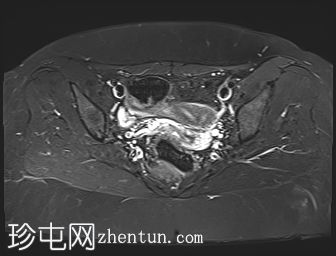

轴位

斜位T2加权像

子宫外底轮廓清晰,肌层较厚,将子宫内膜腔分隔成两个腔,纤维层较薄,向下延伸至宫颈外口。子宫内膜厚度正常,两个子宫腔交界区清晰,未见明显的实性局灶性病变。

本病例展示了典型的纵隔子宫影像学表现:增厚的肌层隔膜将子宫内膜腔分隔成两个腔,并有一层薄的纤维隔膜延伸至子宫颈外口水平,符合完全纵隔子宫的特征。

在MRI图像上,纵隔子宫通常大小正常,但每个子宫腔的形态均小于正常子宫腔。

隔膜可能由纤维组织(T2信号低)、肌层组织(中等信号)或两者共同构成,如本病例所示。